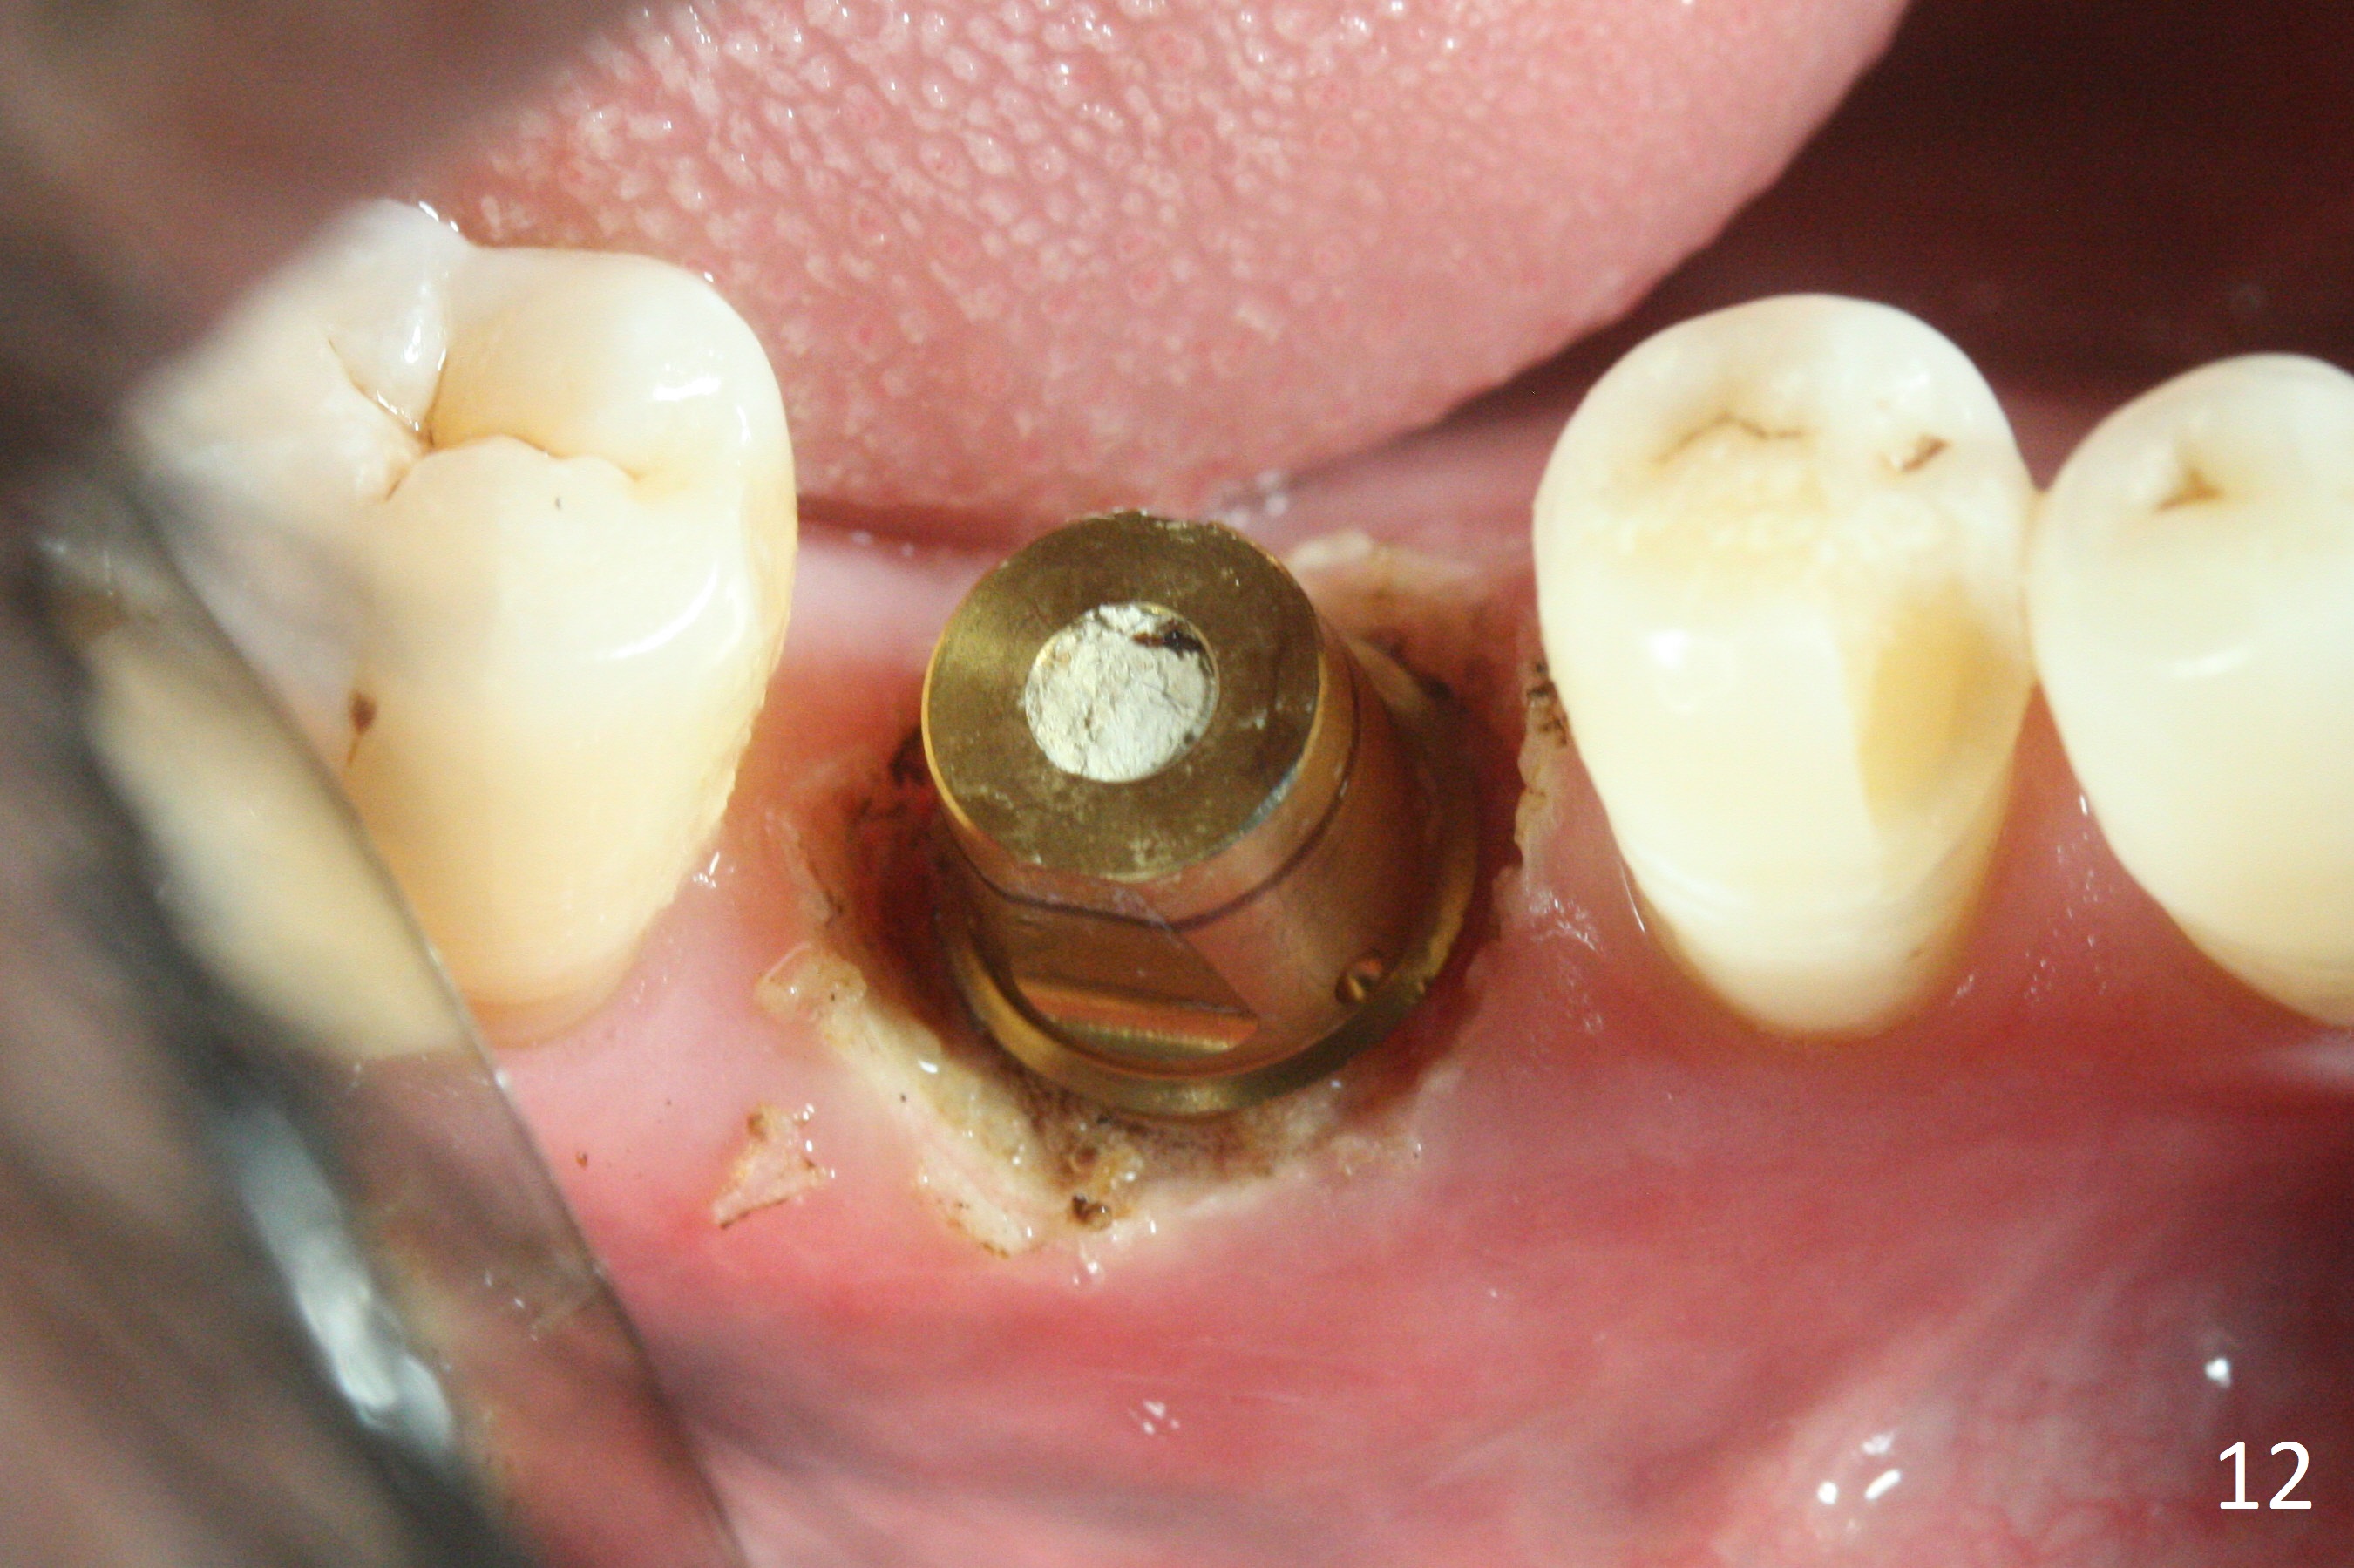

The bone (Fig.10 arrowhead) and soft tissue (Fig.11 *) heal 2 months postop. Gingivectomy is done with Diode prior to impression (Fig.12). The provisional is relined to keep the margin (Fig.13, 2 weeks later) and a permanent crown tries in (Fig.14).